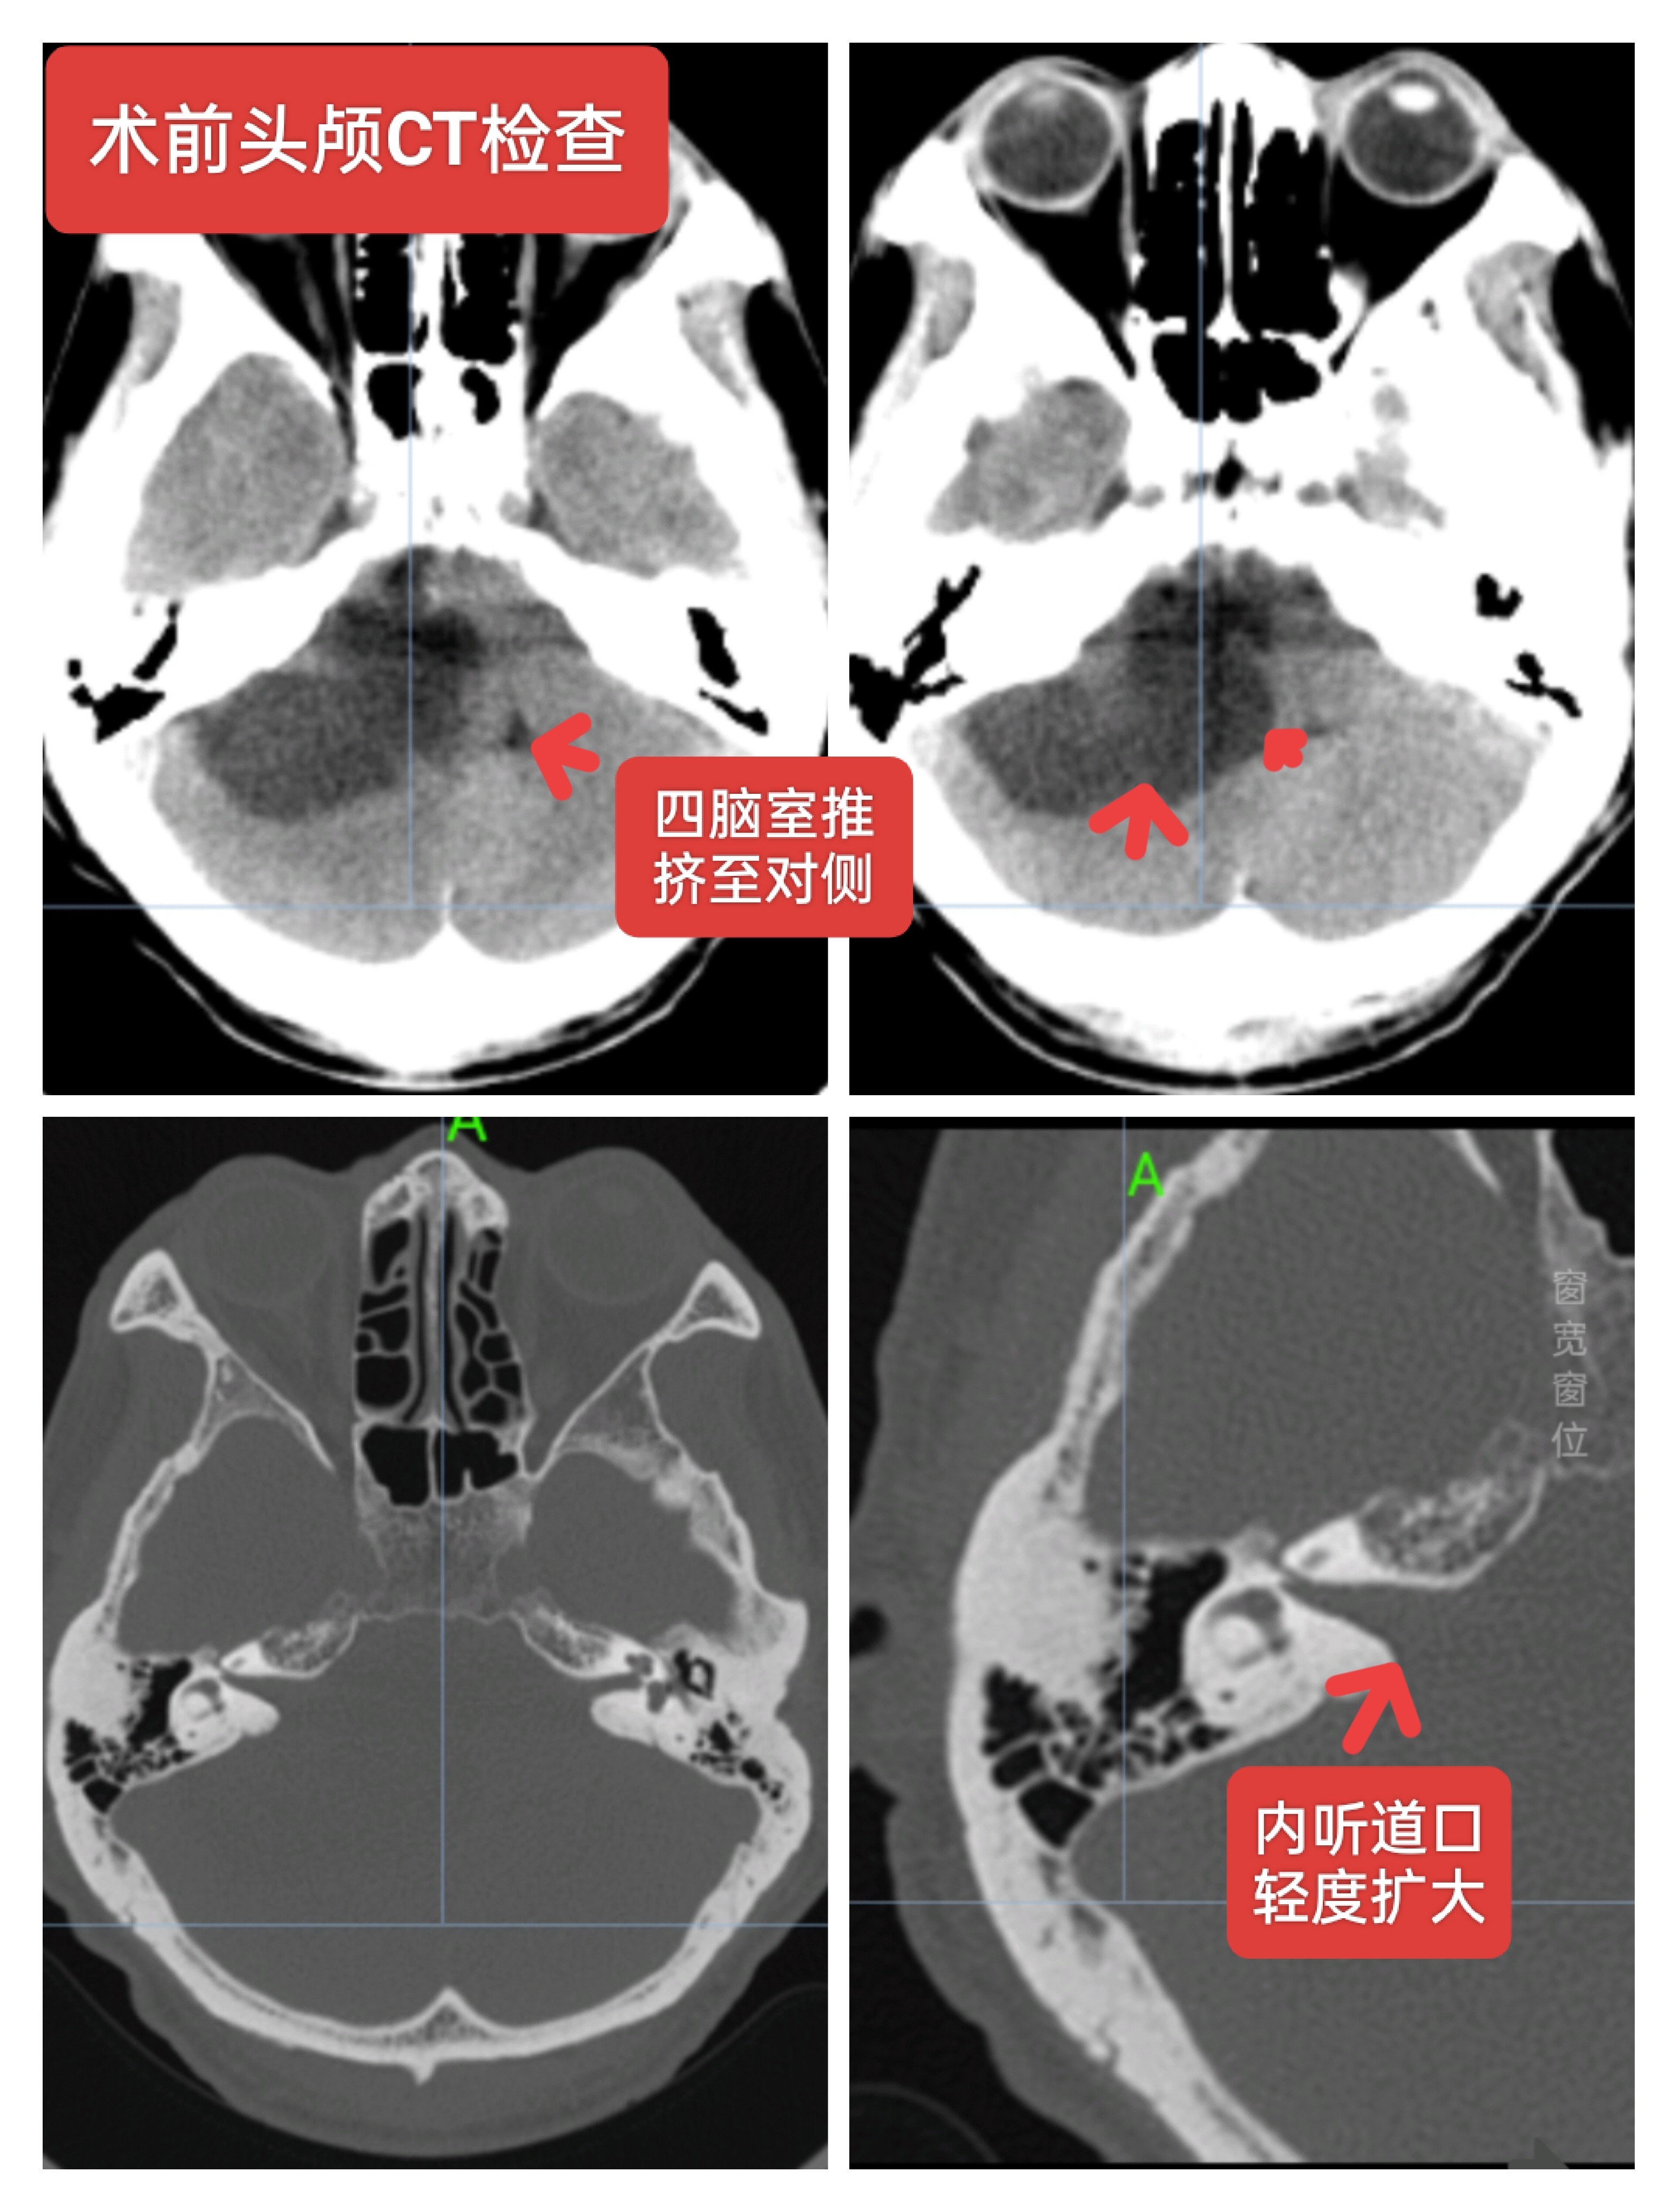

右侧听神经瘤,男性64岁,听力下降一年主诉入院,核磁检查提示右侧CPA区囊实性占位,大小约5cm左右,常规行神经电生理监测下肿瘤切除术,术中面神经保留,术后轻度面瘫。